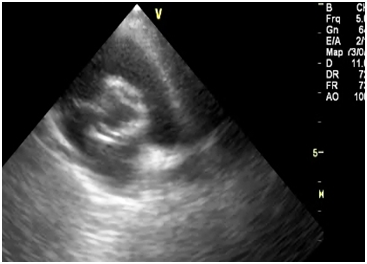

Investigations revealed hemoglobin value of 9g/dL, WBC count 4,000/cumm and platelet count was normal. Liver function test and renal function tests were normal. ECG showed the left ventricular hypertrophy. On chest X-ray there was a normal cardiac silhoutte and a normal lung parenchyma. Transthoracic echocardiography showed parachute-like mitral valve with a severe mitral stenosis (mitral valve size: 0.6 cm2, pressure gradient (Pg: 20 mmHg) causing obstruction to flow Figure 1. Aortic valve was bicuspid with a mild to moderate aortic stenosis (Pg: 40 mm Hg) Figure 2. Severe post-ductal coarctation of aorta with a diastolic tailing was seen on suprasternal view Figure 3. There was a Tiny mid muscular ventricular septal defect with left to right shunt. Small size patent ductus arteriosus with bidirectional shunt mainly left to right was present. Severe tricuspid regurgitation secondary to severe pulmonary hypertension (Right Ventricular systolic pressure = 84mmHg). Pulmonary artery was grossly dilated. There was mild left ventricular hypertrophy with a normal global systolic function and a normal ejection fraction. CT angiography revealed post ductal coarctation of aorta with patent ductus arteriosus with enlarged pulmonary trunk.